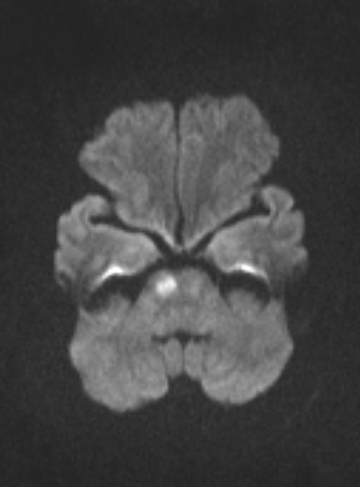

| Hình ảnh Cộng hưởng từ sọ não (MRI) của người phụ nữ bị ong đốt: Với xung khuếch tán Diffusion cho kết quả nhồi máu cầu não phải. Ảnh: BV. |

Tại thời điểm vào, bệnh nhân hoàn toàn tỉnh táo, liệt nửa người trái, chỉ số mạch, nhiệt độ, huyết áp, nhịp thở hoàn toàn bình thường. Tuy nhiên khi thăm khám, bệnh nhân có triệu chứng co giật nửa người liệt, các bác sĩ đã khai thác thêm bệnh sử của bệnh nhân.